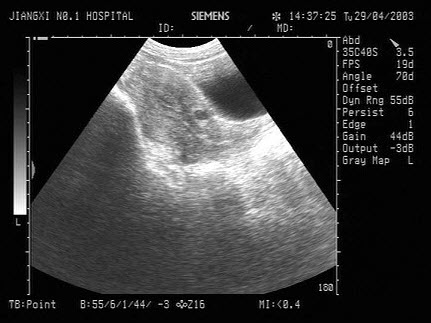

18、单项选择题

如图,初步超声诊断为()